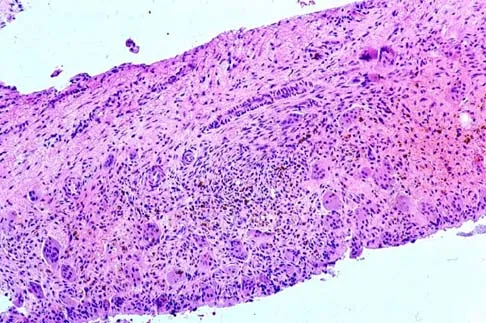

A 16-year-old boy has had thigh pain for the past several months. He denies any history of trauma. Examination reveals a large, deeply fixed, soft-tissue mass in the thigh. Laboratory results show an elevated erythrocyte sedimentation rate (ESR) and leukocytosis. A plain radiograph and MRI scan are shown in Figures 1a and 1b. Biopsy specimens are shown in Figures 1c and 1d. What is the most likely diagnosis?

A 44-year-old man has right hip pain. Radiographs reveal a radiolucent lesion of the femoral head and neck. An MRI scan shows no extraosseous tumor extension. A histopathologic photomicrograph of the biopsy specimen is shown in Figure 5. The chance of metastatic disease developing from this lesion is approximately what percent?